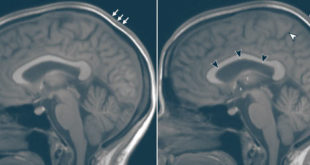

Spaceflight Affects

Study: Long-Duration Spaceflight Affects Brain Volume A new study led by Professor Larry Kramer from the University of Texas Health Science Center at Houston suggests that the impact of microgravity is far-reaching, potentially causing brain volume changes and pituitary gland deformation. Reconstructed sagittal 5-mm orthogonal midline images in the brain …